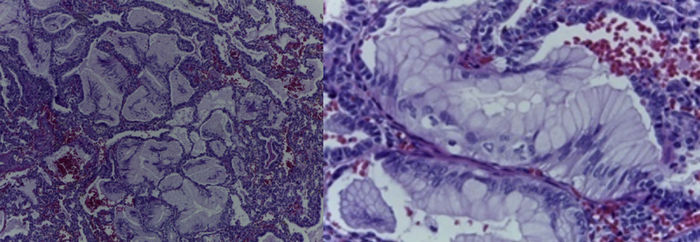

Se observa una pieza quirúrgica que corresponde al lóbulo superior del pulmón izquierdo. Pesó 80 g y presentaba una pleura opaca, despulida y congestiva. A los cortes seriados, se observaron numerosos quistes con un diámetro promedio entre 2 y 5 cm. Entre los quistes había áreas de parénquima pulmonar con congestión importante. Existe un quiste de mayor tamaño, con diámetro de 6 cm, cuya superficie interna es brillante y trabeculada (Figura 3). Otros quistes más pequeños estaban separados por tabiques de tejido conectivo, lo que se corroboró mediante la histología. La malformación estaba constituida por numerosos quistes revestidos por epitelio columnar y epitelio cilíndrico ciliado, que alternaban con algunas células mucosas. Estas células mucosas recuerdan las glándulas intestinales, mucoproductoras; entre estas se observaron tabiques de tejido fibroconectivo con algunas células comprimidas. Entre los quistes revestidos por este epitelio vemos, además, la presencia de músculo liso (Figura 4).

Figura 4 Quistes revestidos por células columnares mucoproductoras y presencia de músculo liso (HE 40X).

Con estos hallazgos, se diagnosticó una malformación congénita de la vía aérea tipo I por el tamaño de los quistes y por la presencia de músculo liso localizado entre los quistes. Cabe mencionar que esta malformación es la que se presenta con mayor frecuencia, aproximadamente en el 70% de los casos. Anteriormente se describían tres tipos. Ahora se sabe que son cuatro. Stocker los describió a partir del 2002, y se clasifican del 0 al 4. El cero es incompatible con la vida, y el cuatro es el extremo.